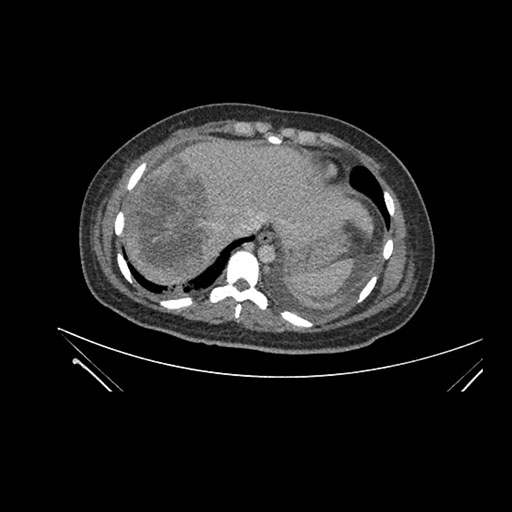

Imaging Analysis

Look through the patient's CT scan to identify any areas of concern for the necessary procedure.

Axial Arterial

Based on initial findings, which issue(s) would you be most concerned about?